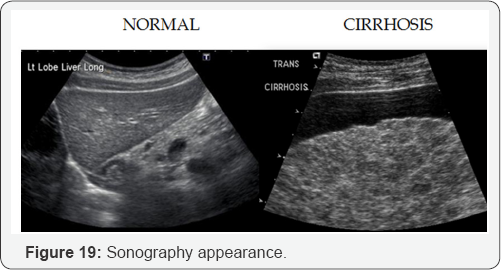

PV dilation due to obstruction. Reverse flow to SMV, IMV, and SV. Blood that cannot enter into PV must return to systematic circulation via anatomotic sites. Results: Esophageal varices, rectal hemorrhoids, caput medusa, etc (Figure 15-29).

B. Sonographic characteristics of cirrhosis:

a. Hyper echoic liver

b. Course texture.

c. Irregular/nodular surface.

d. Small liver

e. Caudate lobe hypertrophy and decrease echogenicity.

f. Non visualization of hepatic veins.

g. Portal vein dilation >13mm.

h. Portal vein reverses flow.

i. Portal vein hypertension.

j. Dilation of splenic veins, SMV, IMV with reverse flow

k. Splenomegaly.

l. Ascites.